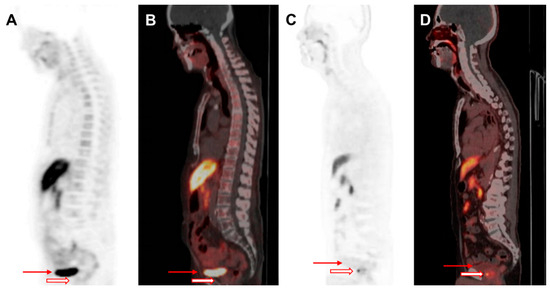

- Lee, J.; Sato, M.M.; Coel, M.N.; Lee, K.H.; Kwee, S.A. Prediction of PSA Progression in Castration-Resistant Prostate Cancer Based on Treatment-Associated Change in Tumor Burden Quantified by F-18 Fluorocholine PET/CT. J. Nucl. Med. 2016, 57, 1058–1064. [Google Scholar] [CrossRef]